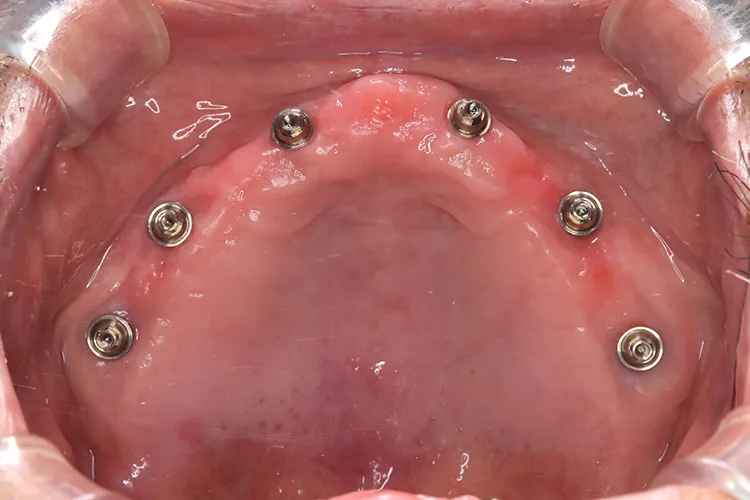

上顎の総入れ歯が不安定で固定式を希望され、インプラント6本で上部構造を支えるボーンアンカードブリッジを選択されました。インプラント埋入したその日にそれまで使用していた入れ歯をインプラントに固定させました。その後歯肉が治癒した段階で最終の上部構造(14本ブリッジ)を装着しました。